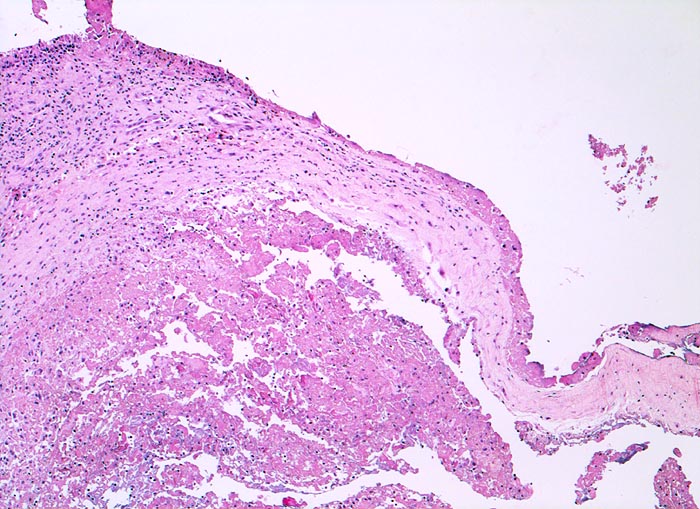

In Abhängigkeit von der Entzündungsdauer werden unterschiedliche morphologische Befunde beschrieben. Die initiale proliferative Phase ist charakterisiert durch eine Hyperplasie der Synovialis, Fibrinexsudate und Gelenkergüsse. In der destruktiven Phase kommt es zur Zerstörung von Gelenkknorpel und gelenknahem Knochen durch Ausbildung eines intraartikulären Pannusgewebes (> 194). Die ausgebrannte Phase ist gekennzeichnet durch eine synoviale Fibrose mit zunehmender Ankylose (= Gelenkversteifung).

Typische histologische Veränderungen sind eine synoviale Zottenhyperplasie, Verbreiterung der Deckzellschicht unter Einschluss mehrkerniger Riesenzellen, Fibrinexsudate und synoviale Ulzerationen, Infiltrate von Lymphozyten teils in Form von Lymphfollikeln, Plasmazellen, neutrophilen Granulozyten, Makrophagen und Siderophagen, sowie Einschlüsse von Knorpel- und Knochenfragmenten (Detritussynovialitis). Die histologischen Befunde der Synovialis korrelieren oft nicht mit den klinischen Angaben. Trotz fortgeschrittener Gelenkdestruktion mit ausgeprägter klinischer Symptomatik können Synovialektomiepräparate nur sehr geringe pathologische Veränderungen zeigen. Oft ist auch nicht mehr zu eruieren, welche Läsionen Folge der Grundkrankheit und welche Folge diverser intraartikulärer Therapien oder begleitender Superinfektionen sind.

• Synovialis mit verplumpten Zotten.

• Stark proliferierte mehrreihige synoviale Deckzellschicht.

• Herdförmig Fibrinauflagerungen durchsetzt von neutrophilen Granulozyten.

• Hyperzelluläres Stroma mit lymphoplasmazellulärem Entzündungsinfiltrat mit Ausbildung von Lymphfollikeln.